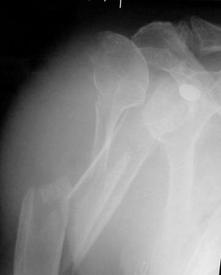

Fractura de humerus

de humerus

Luxatie

gleno-humerala

Fractura proximala

intracapsulara de humerus Fractura proximala intracapsulara de humerus

gleno-humerala Luxatie gleno-humerala